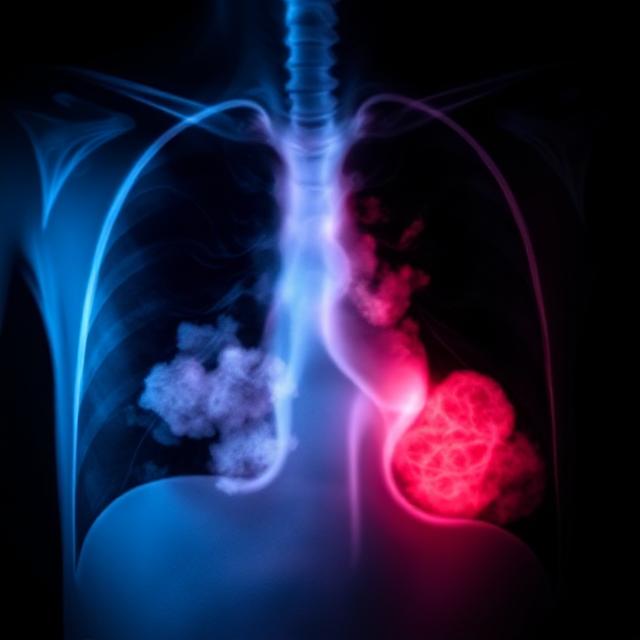

آب آوردن ریه که در اصطلاح پزشکی به آن پلورال افیوژن گفته می‌شود، یک وضعیت جدی است که در آن مایع در فضای بین ریه و دیواره قفسه سینه جمع می‌شود. این مشکل می‌تواند تنفس را دشوار کند و در صورت عدم درمان به مشکلات جدی‌تری منجر شود. در ادامه، به بررسی علت‌ها، علائم، روش‌های درمان و نکات مراقبتی خواهیم پرداخت.

آب آوردن ریه می‌تواند ناشی از شرایط مختلف باشد، از جمله بیماری‌های قلبی، عفونی و سرطانی. رایج‌ترین علل عبارت‌اند از:

سرطان تومورها، به ویژه سرطان ریه و پستان، می‌توانند باعث تجمع مایع شوند.